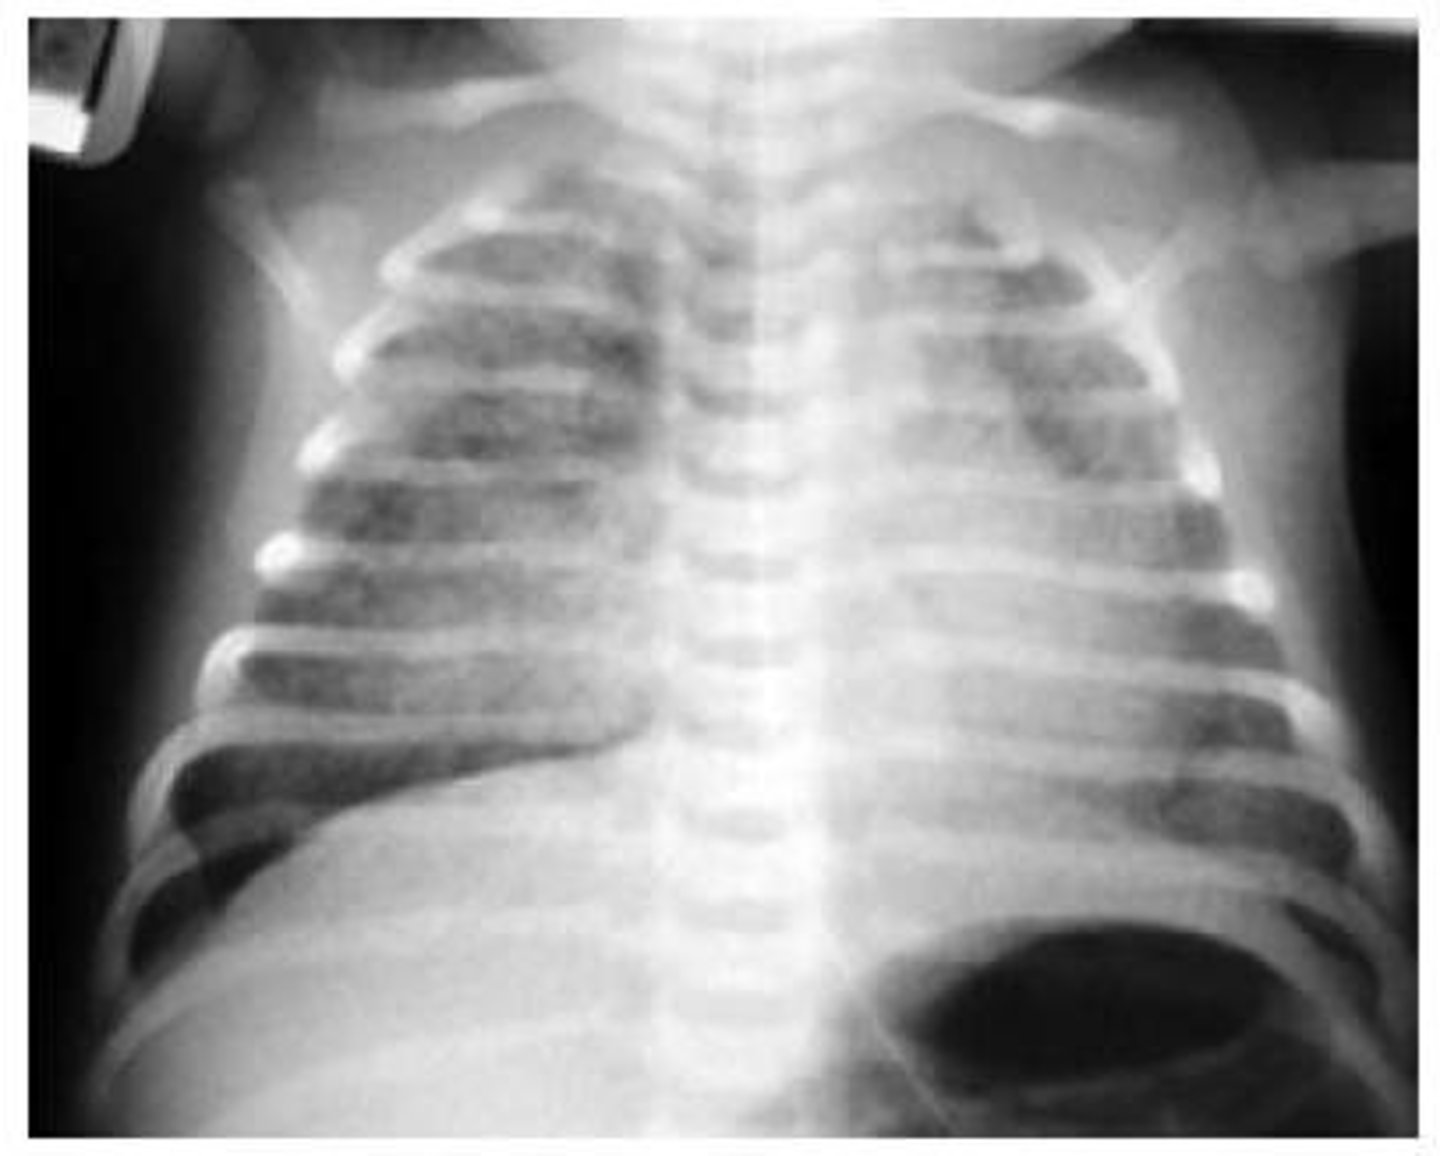

TTN

Pathophys: Lung fluid not squeezed out, retained

Prognosis: Usually minimal O2 needed. Self resolves in hrs to days

38 wk LGA infant born by C/S to an A2GDM has dyspnea/grunting

- Pathophys?

- Prognosis?